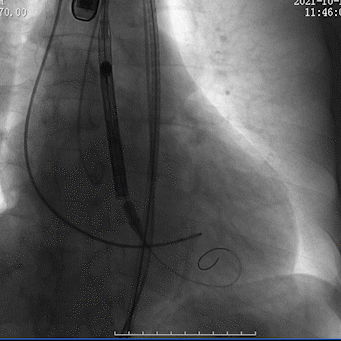

瓣膜回收调整位置

瓣膜再定位

瓣膜植入较深

瓣膜再回收调整